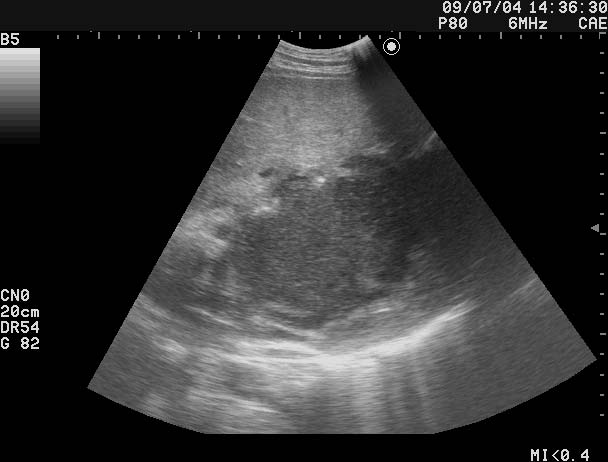

Все верно, абсцесс печени

Дренирован, динамика - см по числам в правом верхнем углу сонограмм